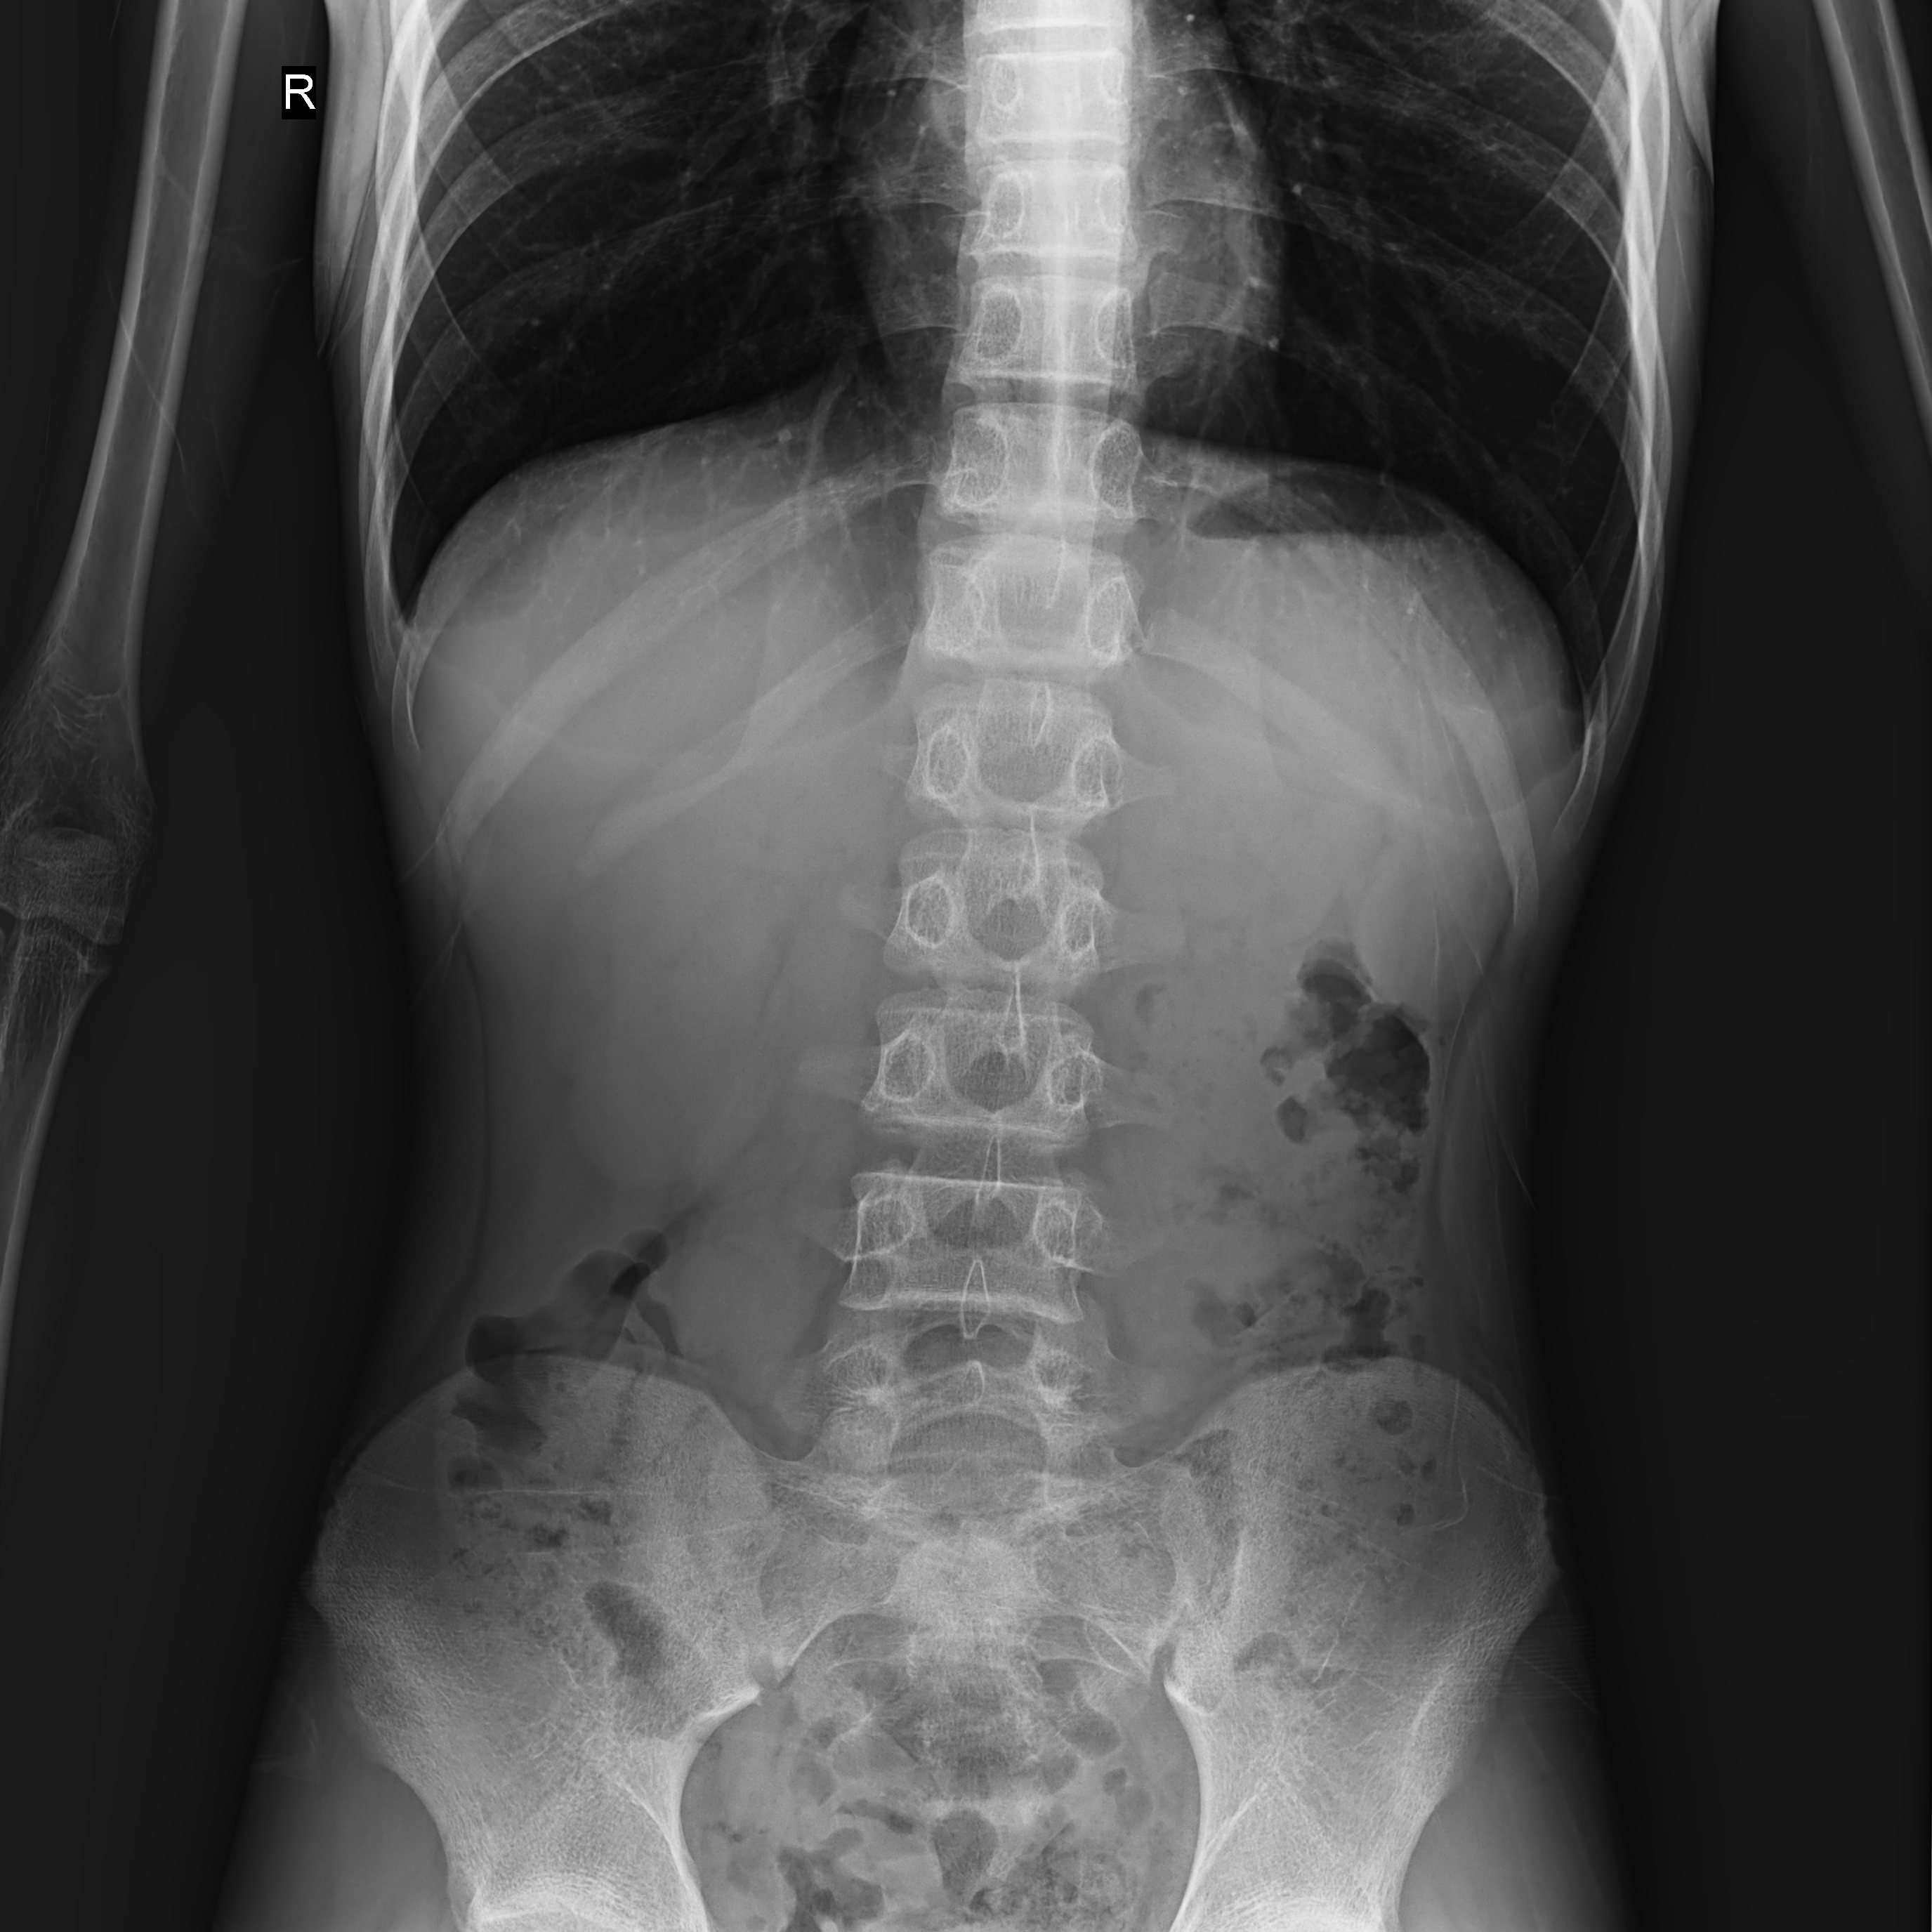

腰